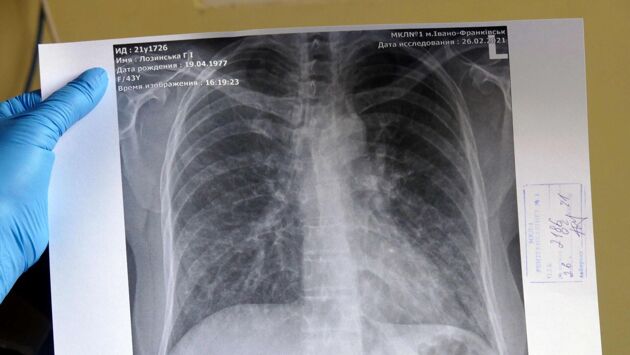

Врач Ким: три симптома могут указывать на развитие микоплазменной пневмонии

На развитие микоплазменной пневмонии указывают следующие симптомы: сухой кашель, першение в горле и лихорадка. При их появлении необходимо сразу же обратиться к врачу. Об этом «Газете.Ru» рассказала ассистент кафедры госпитальной терапии Института материнства и детства Пироговского Университета, врач-терапевт Татьяна Ким.

По словам врача, микоплазменная пневмония вызывается респираторной микоплазменной инфекцией, атипичным бактериальным микроорганизмом. С начала осеннего периода возникло несколько вспышек микоплазменных пневмоний в этом году, несмотря на то, что микоплазменная инфекция может быть возбудителем до 20% случаев пневмоний.